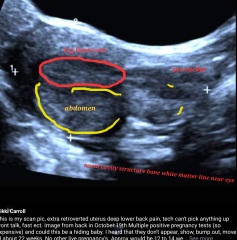

Hi All, I haven't been back on for a bit I been feeling crazy and anxious and a bit crappy. I went for another ultrasound and basically the same thing has happened as I get bigger and cravings approx 17 weeks and still silence to concentrate on the scan I feel silenced. I'm in the midst of seeking a 2nd opinion and trying to settle myself and find motivation and energy but my instincts and intuition are driving me to find answers. Otherwise from strong pregnancy symptoms religiously by the book to the fine tune. My uterus is still retroverted and flexed, I'm having terrible back ache and swimming to see if it might position forward and gentle yoga. Once again it's been said in literature that retroverted uterus babies may not be seen until 20 weeks, movements on 22 to 24 weeks and showing a very late bump so I'm,waiting. Still abstinent and presented to the ER thus week from dizzy spells and fainting feelings. BP good, GTG of heart good nothing else again sent home without back relief or advice to manage. I nearly fainted walking to collect mail the other day saw stars and staggered back inside. Anyone have any further ideas besides getting another opinion please I thought I seen a face on pic on the last scan different and bigger than my October one on edge. Even once I thought it was a head lying transverse across abdomens and leg bent over the body.

MissBee02 · 29/11/2022 17:51

At one timemi thought this was the potty shot and was bent over perfectly before scribing on it. Its the same a s above. The pic in the edge though with little beam eyes and a face has really got me almost upright maybe tucked into the titled uterus at the curl end ...I have no idea maybe it's small maybe it's big and I'm totally missing it maybe I'm seeing things. I just want to get on with my life 😩

@MissBee02 if you could see anything that was part of a fetus then a trained sonographer could see it too, so I would worry you are misreading images.

@MissBee02 have they offered you a transvaginal ultrasound as I know that can help identify with a retroverted uterus . ( I remember from a thread a long time ago a woman had mentioned that she was offered one due to her retroverted uterus ) .

Thankyou all Prolactin levels done and are good, also HCG levels are on track, rose and doubles then starting to decline slowly now not so much significantly. I will be ok, I guess I will wait til I feel movement and of I from bigger put the 2 together and stomp and down. My providers need to talk and keep us informed. All other pathology is great and internal organs great. TV scan was used I my 1st pregancy in January this yr and it aggravated the cervix or placenta that made me spot and light bleed after so they don't recommend anymore. Thanks all. I will get clarity soon or maybe something will move forward visible around 20 + week. There's no denying th a t unique movement feeling and kicks too I have friends who have told me Xx